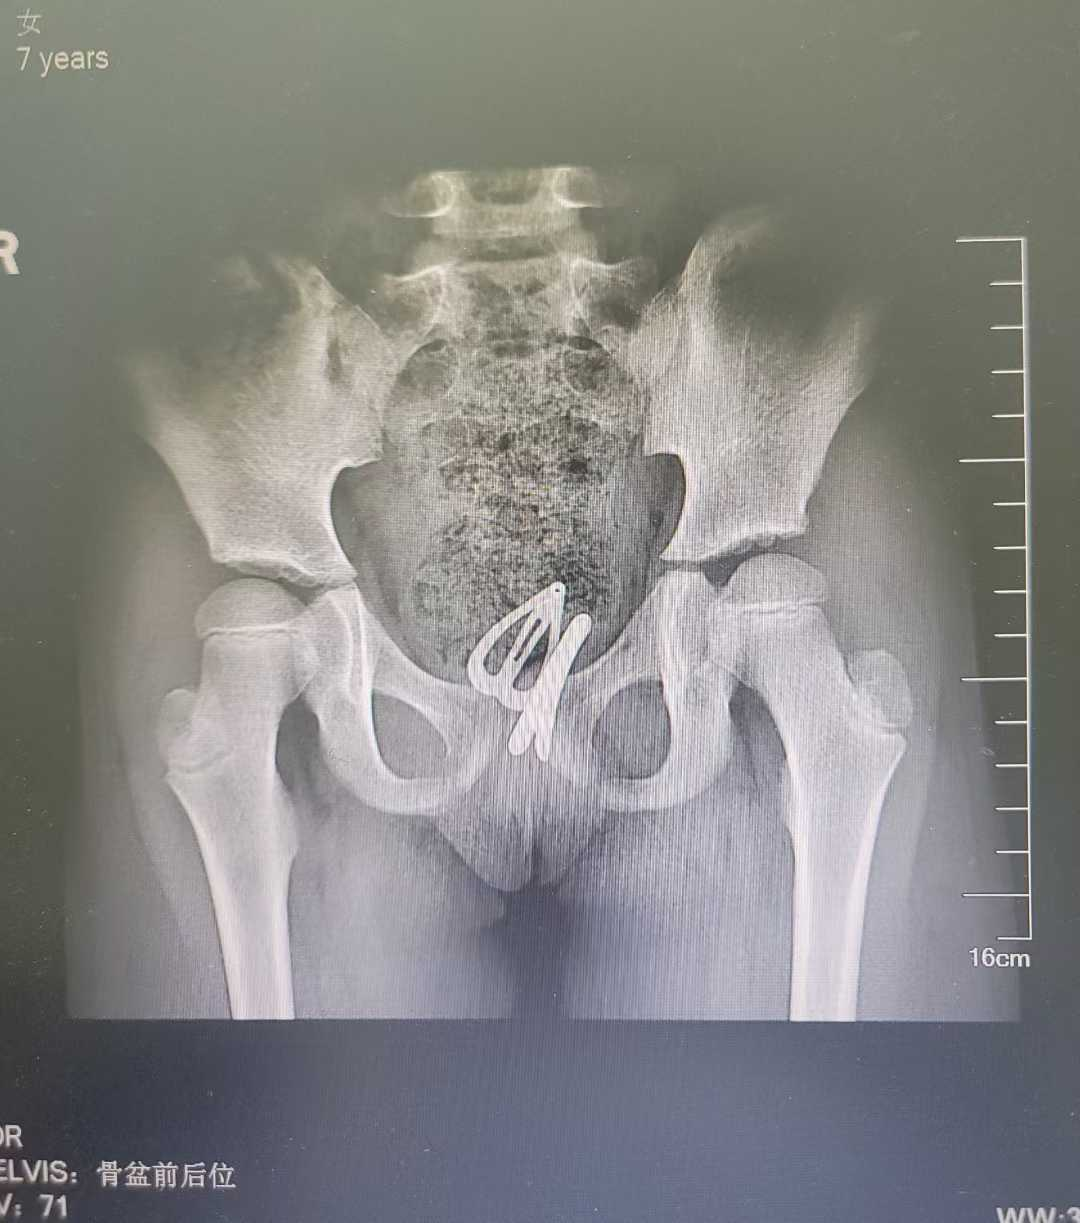

近日,广西壮族自治区南溪山医院小儿青少年妇科门诊接诊一名特殊的 7 岁小患者,该患儿因反复异常阴道流液 5 个月,在当地多家医院辗转诊治均未痊愈,慕名前来我院就诊,经详细检查确诊为阴道异物,医护团队通过阴道内镜微创技术成功取出两枚发卡及一枚橡皮圈,术后患儿症状即刻消失,目前已顺利康复。

南溪山医院医护团队制定精准诊疗方案,采用阴道内镜微创技术开展手术,为最大限度减少对患儿身体的损伤。术中,医护人员精准置入外鞘直径仅 3.5mm 的宫腔镜,在高清视野下仔细分离异物周围粘连组织,小心翼翼操作,最终将深藏于阴道内的两枚发卡与一枚橡皮圈完整取出。随着异物彻底清除,困扰女童近半年的阴道流液问题也随之迎刃而解。

下图为术中所见,置于阴道顶端的发卡。